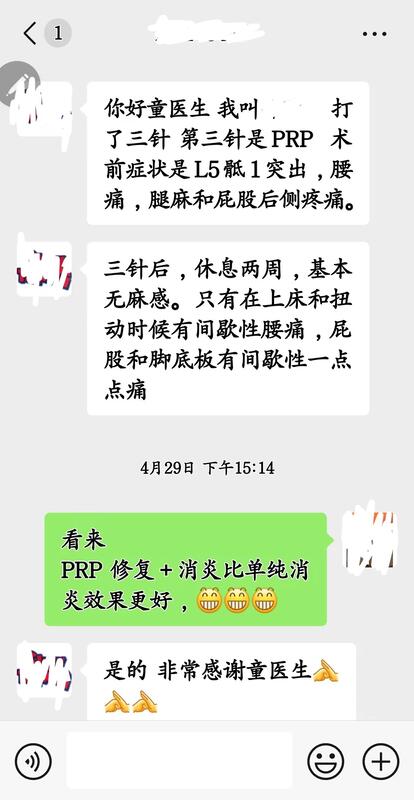

2次:消炎-童氏精准无创介入治疗

1次:修补+消炎-PRP

1个月后:患者康复

患者住院一周,做了二次童氏精准无创介入治疗出院

二周后再次住院二天,做了一次PRP后出院(见图2)

二周后,奇迹出现了;

2次童氏精准无创介入治疗

1次PRP治疗

在这位患者身上奇迹出现了

1个月左右患者康复了。

2+1=1

我们成功了